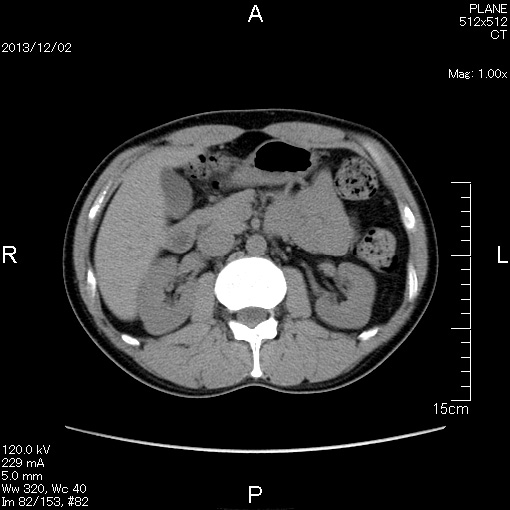

マーカー、CT画像、問題なし!!

左から2013年12月、2013年06月、2012年12月と背骨の位置は合わせて並べてみた。

6月まではあまり変化がなかったが、この半年で明らかに違う。

背中側の脂肪がやや増えてはいる。

でも最も大きな違いは、腸なのか、やたらと内臓が膨れている・・・。

一言で言うと食べすぎ?!?!

食事は野菜中心ではあるが、確かによく食べているw。

半年に一回の定期検査である。

6月より太ったからCT画像の腹脂肪が気になる・・・。